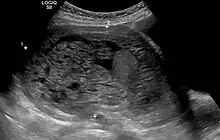

- Molar pregnancy in ultrasound